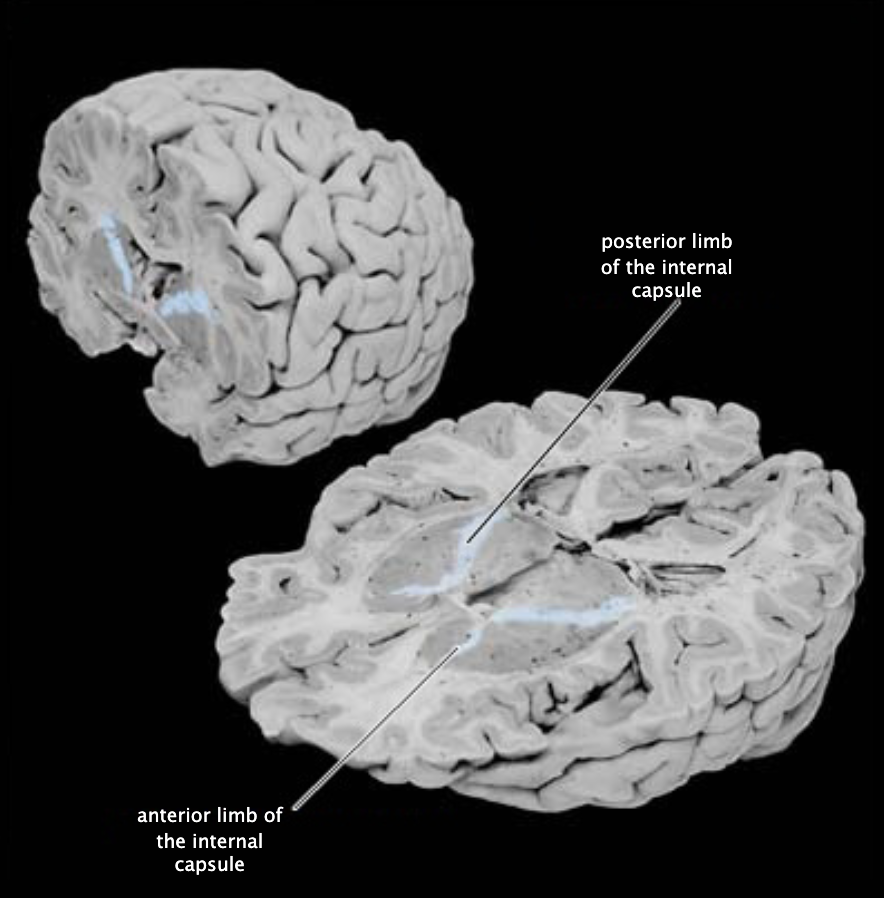

Internal capsule

Large white matter structure that lies between the diencephalon and the basal ganglia comprising numerous cortical and thalamic projection fibers, including sensory axons that run from the thalamus to the cortex and motor axons that run from the cortex to the brainstem and spinal cord.

Internal capsule, anterior limb

Anterior portion of the internal capsule that lies between the caudate nucleus and the putamen.

Internal capsule, posterior limb

Posterior portion of the internal capsule that lies between the putamen and the thalamus.